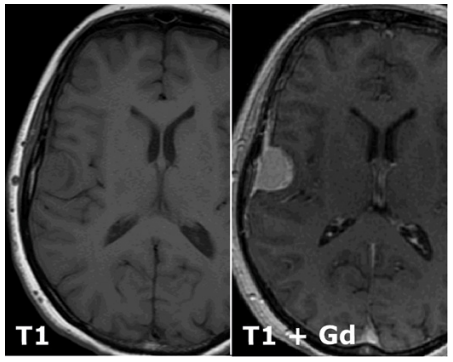

What is a T1 MRI scan and how does it differe from a T2 scan?

T2 is basically T1 but inverted.

T1 shows water dark

T2 shows water bright

Desribe what can be seen. What might it be, and which tissue might it derive from?

A meningioma of the right hemisphere deriving from meningiothelial cells.

Why does gadolinium enhance the lesion?

Gad enchances blood vessels and the tumour will be highly vascular

Which structures in the cerebral hemispehre is the lesion compressing?

The frontal lobe and the primary motor cortex